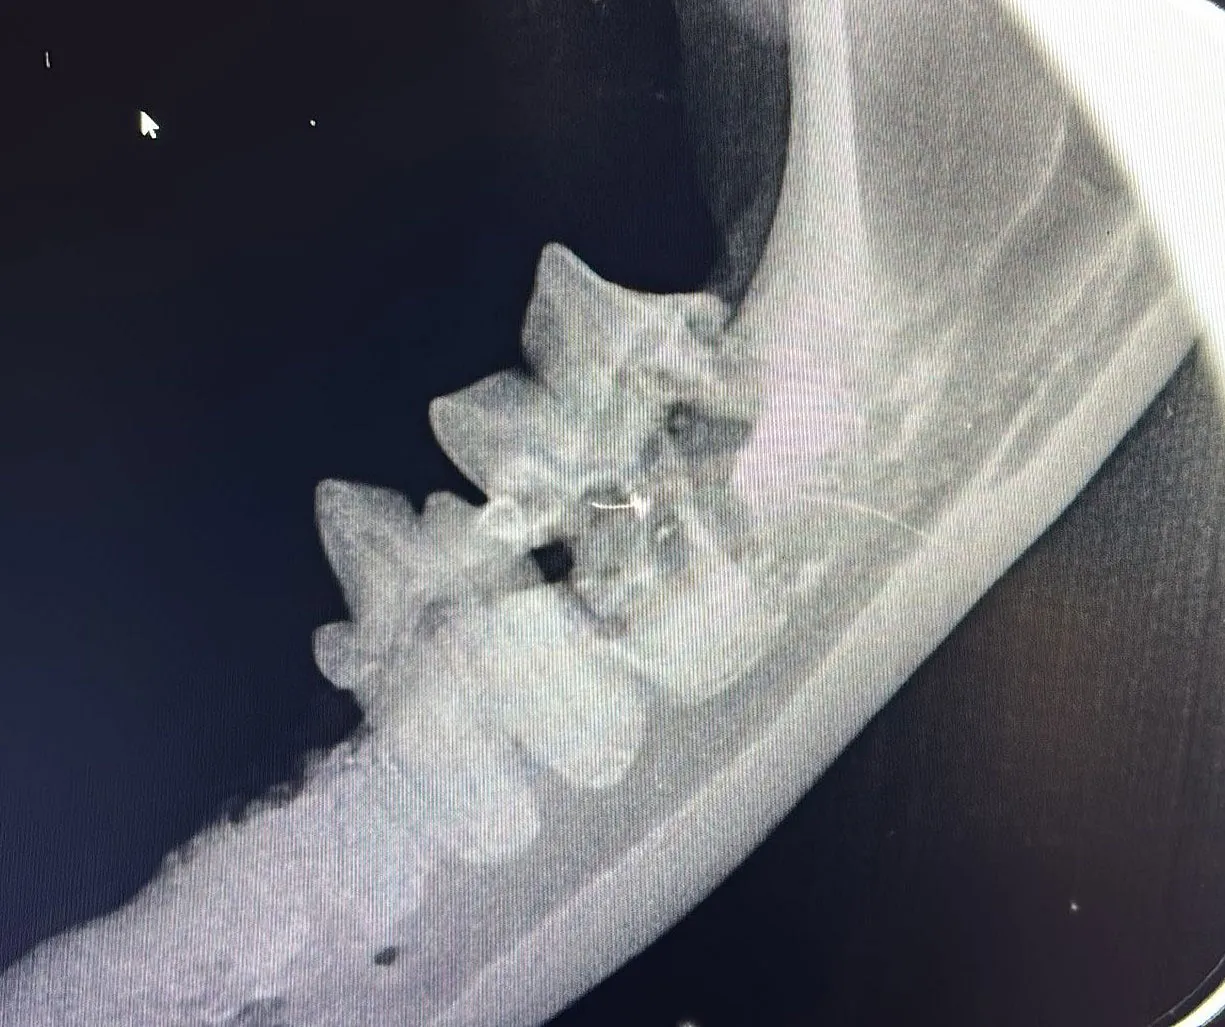

Dentalröntgen – der Goldstandard

• Digitale Zahnradiografie aller Zähne

• Beurteilung von Wurzelresorption, FORL, Abszessen und Frakturen

• Diagnose auch bei äußerlich unauffälligen Zähnen